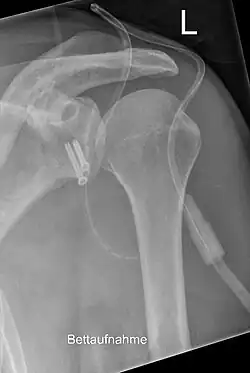

Eine Glenoidfraktur, die die gesamte Schulterpfanne betrifft, entsteht dagegen meist durch einen Unfallmechanismus mit einer sehr hohen Aufprallenergie, etwa bei einem Verkehrsunfall.[5] Begleitverletzungen des Schlüsselbeins, des Brustkorbes, des Armplexus und der Halswirbelsäule sind nicht selten. Zur genauen Diagnostik ist meist eine Computertomographie unerlässlich. Bei einer Verschiebung der Fragmente von 3 mm oder mehr ist eine operative Reposition und Osteosynthese indiziert, um eine vorzeitige Arthrose durch die nicht korrigierte intraartikuläre Stufenbildung zu vermeiden. Die Fixierung erfolgt in der Regel mit Fäden, Drähten, Schrauben oder Platten, die entweder mittels einer arthroskopischen oder einer offenen Operation eingebracht werden.

Meist heilt die Fraktur ohne eine größere Bewegungseinschränkung, in 75 % werden gute Ergebnisse erzielt. Die Gefahr einer Schulterarthrose hängt von der Größe des Knorpelschadens und der Qualität der operativen Rekonstruktion ab. Bei der Operation besteht zudem ein erhebliches Risiko für Verletzungen wichtiger Nerven und Gefäße. Zur Vermeidung einer Einsteifung der Schulter durch Schrumpfung der Gelenkkapsel sind frühzeitig physiotherapeutische Übungen notwendig.